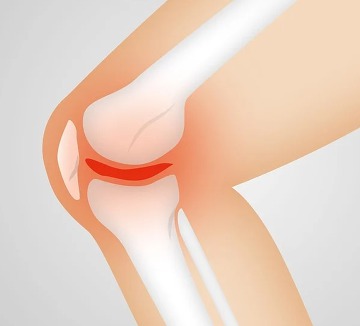

슬패골밑에 있는 경골조면에서만 통증이 나타나고 강합 압통이 주 증상 입니다. 국소적인 열감과 함께 붓는 느낌이 들면서 뼈가 튀어나온 것을 확인할 수 있습니다.

무릎 앞쪽 약간 아래가 아프고 부으면서 무릎 아래에서 뼈가 돌출되는 것이 보인다면 오스굿씨 병 의심해 볼 수 있습니다.

X-ray 검사를 합니다. 성장단계에 따라 크기는 다르지만 경골조면 즉 무릎의 바로 아래에 국한된 골단핵 변화, 유리골편이라는 것이 보여집니다. MRI검사를 하면 연골부를 덮고 있는 슬개건이 두꺼워져 있거나 주변 염증성 변화를 확인할 수 있습니다. 초음파로도 돌출된 뼈와 인대 비후도 볼 수 있습니다.